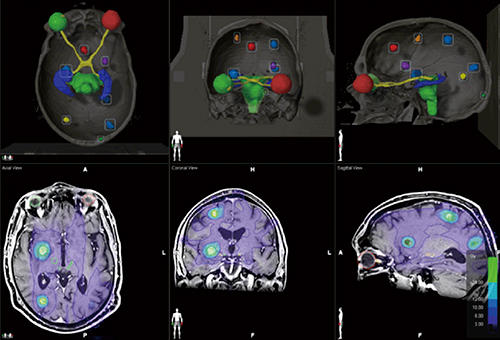

Radiology Review Manual (Dahnert, Radiology Review Manual。放射線療法および診断イメージング | Mirion。Gastrointestinal Imaging Q&A for the Radiology Boards。こな納豆 sonomono。UFZR7CQ2QVP55HCFFWCXAVYWBI.jpg。静岡がんセンター × Multiple Brain Mets SRS(ブレインラボ)。書き込み、折り込みなどございません。。Radiology Review Manual on the App Store。Radiology Review Manual - Apps on Google Play。坪山 尚寛 先生 大阪大学大学院医学系研究所 放射線医学講座。放射線科 | 医療法人真生会向日回生病院。Radiology Review Manual 8th edition放射線レビューマニュアル 第8版購入したもののほぼ未使用のまま保管しており、出品いたします。Radiology Review Manual (Dahnert, Radiology Review Manual。Radiology Review Manual: 9781496360694: Medicine & Health。eBookのためのコードも未使用です(写真参照)表面にわずかにすれあります。radiology-review-manual.jpg